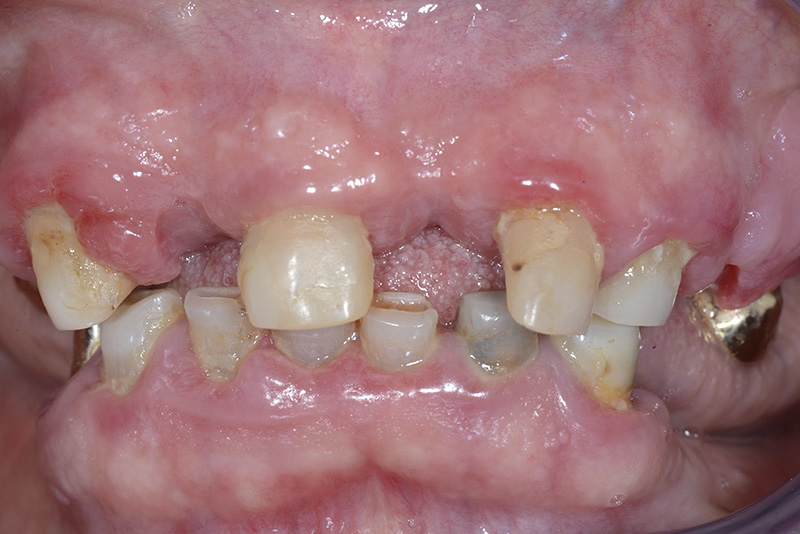

PREMESSA: in seguito all’estrazione dell’incisivo laterale superiore di destra, resasi necessaria per cause batteriche, si decide di affrontare il caso con il posizionamento di un impianto in sostituzione dell’elemento mancante dopo guarigione del sito infetto. Con tecniche rigenerative sia dei tessuti ossei mancanti a causa dell’infezione pregressa, sia dei tessuti gengivali che appaiono inizialmente troppo spostati in alto, si ripristina una corretta morfologia delle parabole (contorni) gengivali e delle papille interdentali (triangoli di gengiva tra due denti vicini).

Vengono utilizzati 2 tipi di provvisori: il primo, cementato ai denti vicini, viene utilizzato dal momento dell’estrazione del dente fino ad impianto osteointegrato (circa 6 mesi); il secondo, avvitato direttamente all’impianto, ha una funzione di prova estetica ma soprattutto di guida per la maturazione dei tessuti gengivali peri-implantari portandoli verso la maturazione completa prima di posizionare la corona finale in disilicato di litio.